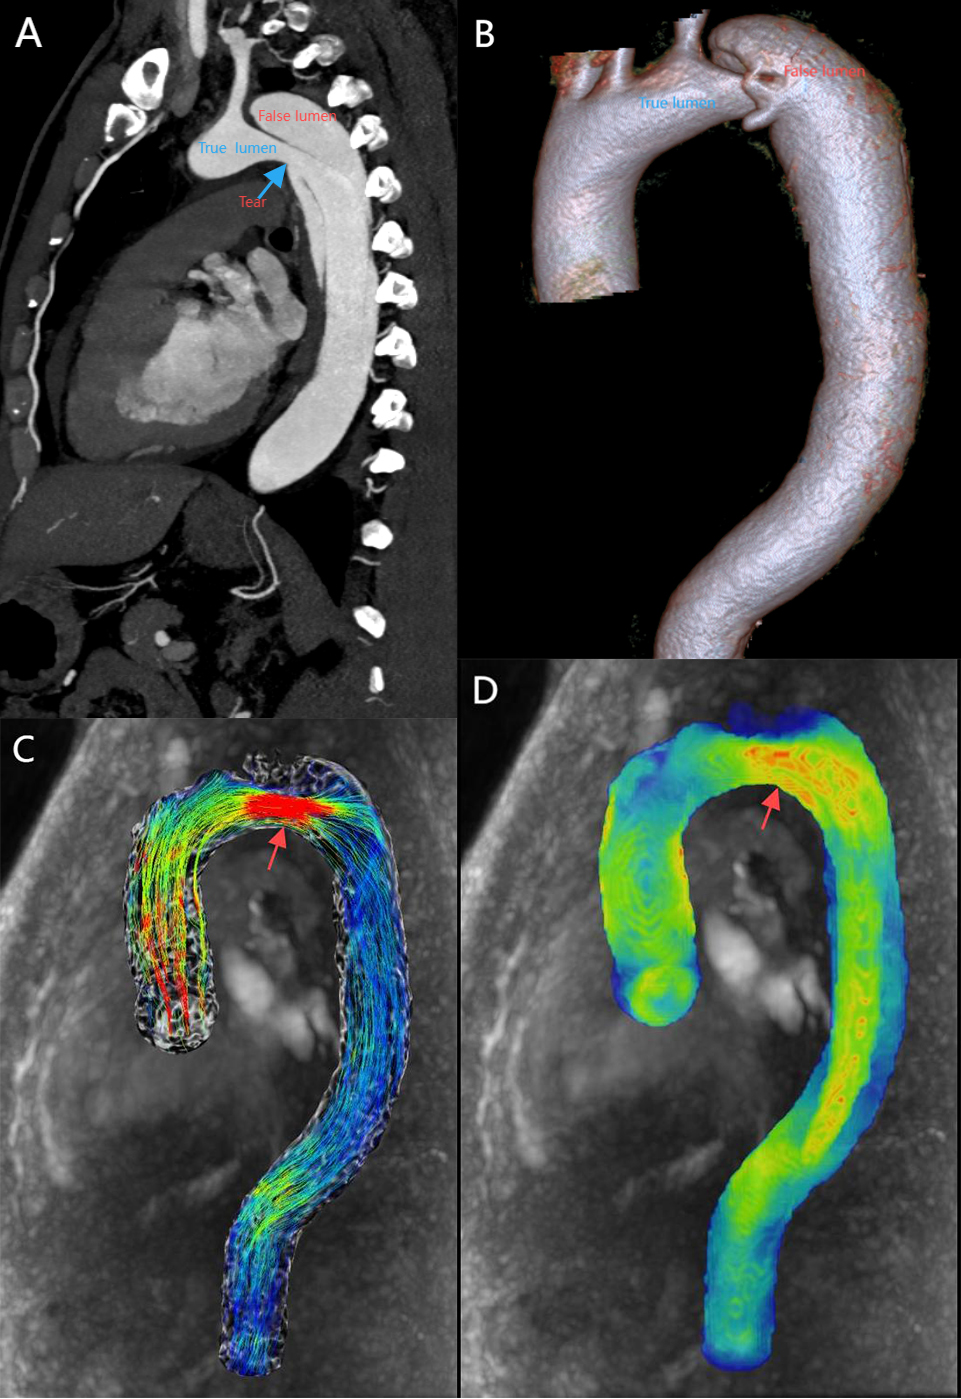

Efficient post-processing software is essential for the quantification and visualization of hemodynamic parameters in both scientific research and clinical applications. The example of 4D flow MRI–based visualization of aortic hemodynamics is shown in Fig. 1. Current post-processing software includes CAAS 5.1 (Pie Medical Imaging, Maastricht, Limburg, the Netherlands), CVI42 6.0.2 (Circle Cardiovascular Imaging, Calgary, Alberta, Canada), GT Flow 3.1.14 (GyroTools, Zurich, Switzerland), iT Flow 1.9 (Cardio Flow Design Inc., Chiyoda-ku, Tokyo, Japan) and MEVISFlow 10.3 (Fraunhofer MEVIS, Bremen, Germany). In addition, some researchers have developed advanced flow analysis parameters using MATLAB R2022b (MathWorks Inc., Natick, MA, USA) or other programming languages to visualize the advanced flow data using post-processing tools in the field of fluid dynamics, such as Ensight and Paraview. It is important to note that there are significant differences in WSS quantitative reference values derived from different post-processing software [16]. These discrepancies may be related to variations in background phase offset corrections, contour splitting, and software algorithms.

Fig. 1. 4D flow magnetic resonance imaging (MRI)–based visualization of aortic hemodynamics in a healthy volunteer. (A) 4D-flow-Image streamlines for the aorta. (B) 4D-flow-Image wall shear stress for the aorta. The color gradient change reflects the magnitude of velocity and wall shear stress (WSS). Red and blue are the maximum and minimum values, respectively. 4D, four dimensions.